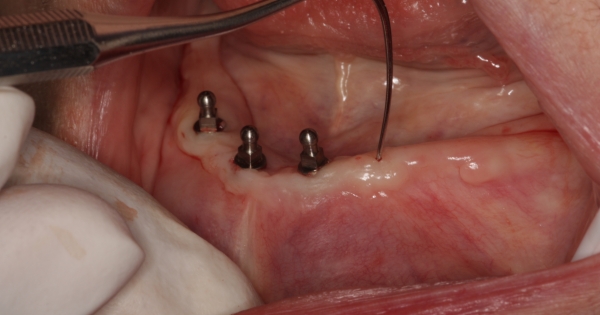

为了变美,有人愿意付出难以想像的代价。下面这个女孩就觉得自己的牙齿不好看,所以决定将牙齿全部拔掉,钻下铁块后衔上整齐洁白的假牙。医生将手术的过程全部拍摄下来,血腥的画面…